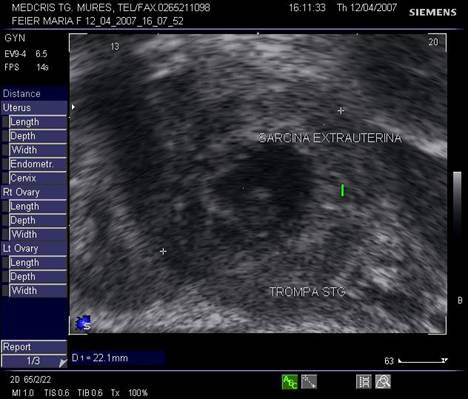

Fig nr 62 Sectiune transversala la nivel corpului uterin , la ecografia transvaginala. Parauterin, in trompa stg., se evidentiaza o formatiune inomogena cu ecou hipoecogen relativ central

![]()

Fig nr 63

Aceeasi sarcina extrauterina oprita in evolutie ca in fig precedenta, marita cu

zoom. Se observa ( cu sageata ) un

embrion pe cale de liza ,situat decliv in sacul gestational .